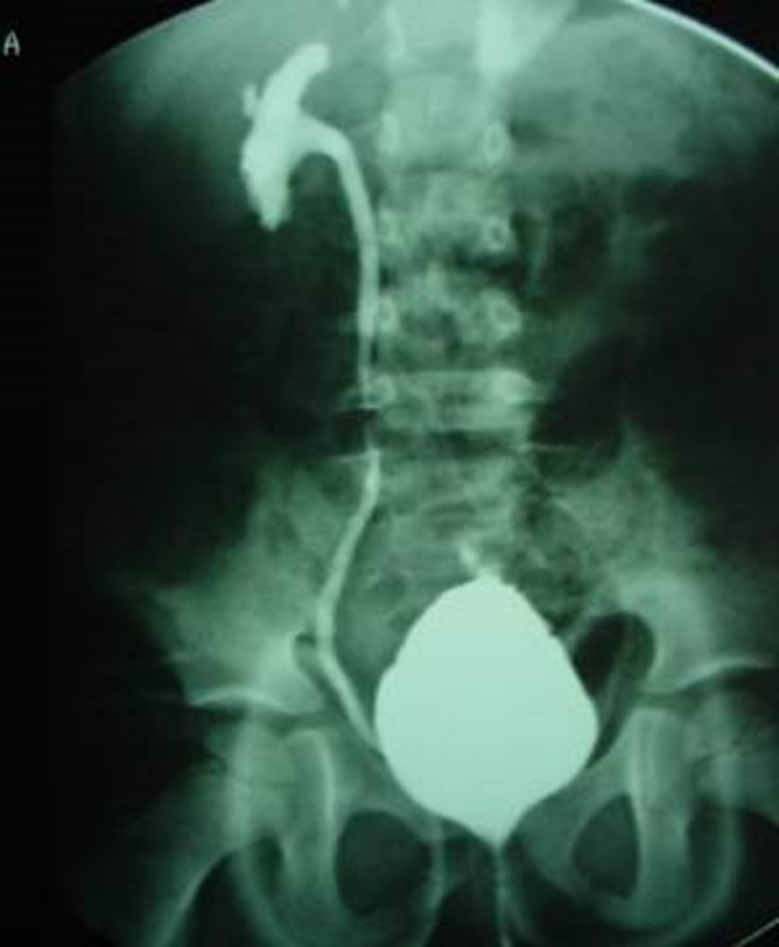

El diagnóstico de reflujo se realiza mediante la realización de una prueba denominada Cistouretrograma de vaciamiento o VCUG. Esto implica colocar un pequeño catéter en la uretra del niño y tomar rayos X de la vejiga usando un contraste "tinte" durante el llenado y durante la micción. El niño necesita estar despierto para saber cuando la vejiga se siente llena. El niño también necesita poder orinar durante la prueba. Se anima a los padres a permanecer cerca de su niño durante la prueba para la comodidad. Los niños con reflujo también tendrán ultrasonidos rutinarios de los riñones y la vejiga para evaluar el crecimiento renal y la presencia de hidronefrosis o dilatación del riñón.